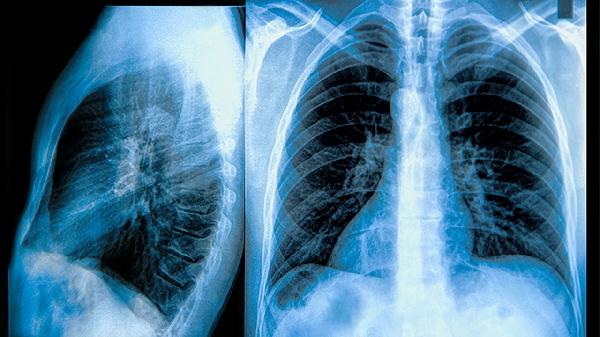

少数情况下,如肺部手术后有明确肺结节残留或尘肺并发症,经胸外科或呼吸科医生综合评估后,可能建议在术后稳定期(通常2-4周后)开始服用。此时需严格监测肝功能、凝血功能等指标,避免与抗生素、免疫抑制剂等药物相互作用。